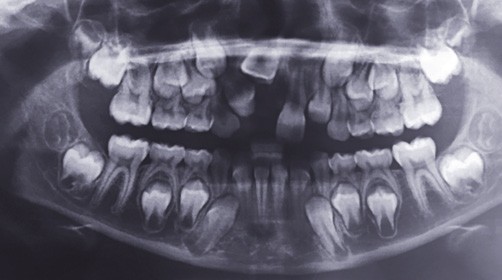

Une dent incluse proprement dite est « une dent encore incluse dans l’os maxillaire ou mandibulaire dont l’édification radiculaire apicale s’est terminée avant que le processus d’éruption ne lui ait permis d’évoluer jusque dans le milieu buccal, sans la moindre effraction de la muqueuse orale et sans contamination du sac péricoronaire par la flore bactérienne buccale » (fig. 2). Une dent en désinclusion est définie comme une « dent restée incluse, une grande partie de la vie, jusqu’à ce que certaines transformations morphologiques de la cavité orale favorisent son exposition au milieu buccal » (fig. 2).